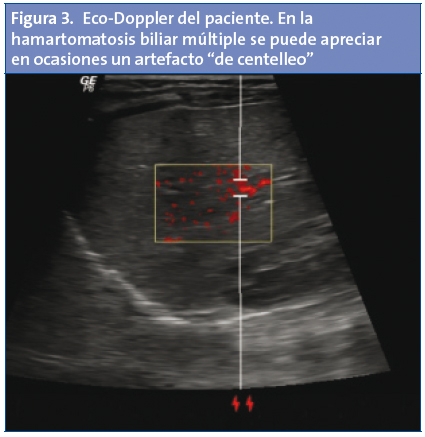

El diagnóstico de la HBM requiere inicialmente una prueba de imagen (ecografía, tomografía computarizada [TC] o resonancia magnética [RM])1-6. En la ecografía, la presencia de hamartomas múltiples hace que el hígado muestre un aspecto granular, heterogéneo, en el que destaca la presencia de numerosas áreas redondeadas hipoanecoicas con zonas hipercogénicas, artefacto en “cola de cometa” y refuerzo posterior. Con el eco-Doppler (Fig. 3) se puede visualizar un artefacto “de centelleo” (alternancia de color inmediatamente detrás de un objeto ecogénico estacionario), debido a las reverberaciones producidas por los cristales de colesterol que rellenan en ocasiones los conductos dilatados1-7. En la TC se aprecia la presencia de múltiples nódulos hipodensos8. Se ha postulado, especialmente en pacientes adultos, que la técnica de elección es la RM. Esta técnica aporta mayor sensibilidad y especificidad a la hora de hacer el diagnóstico diferencial con otros cuadros (Tabla 2). En la secuencia T1, los hamartomas se muestran como estructuras nodulares hipointensas con respecto al parénquima adyacente. En la secuencia T2 se ven como estructuras hiperintensas. Típicamente, los hamartomas no se comunican con la vía biliar, al contrario de lo que ocurre en la enfermedad de Caroli.